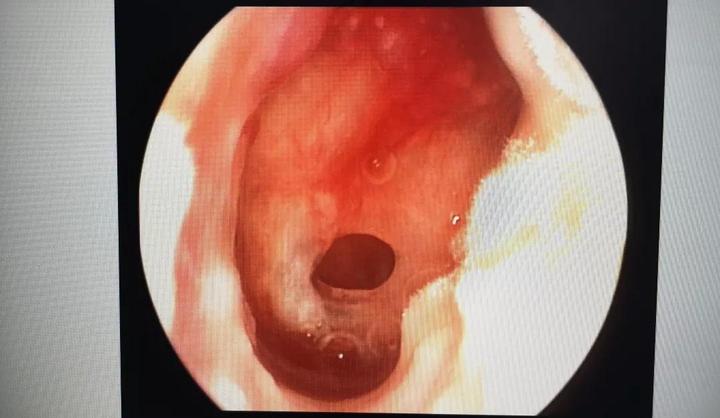

赵小姐家住三墩附近,前两天天气热,就去了家附近的游泳馆去游泳。上周五,赵小姐游泳回来感觉右耳朵疼、发闷,伴有流脓,于是来到三墩院区耳鼻咽喉科就诊。在耳内窥镜下,浙江医院耳鼻咽喉科吕慧洋医师发现,赵女士右侧外耳道通畅,耳道内可见淡黄色脓性分泌物,右侧鼓膜穿孔,鼓室内可见少量积液,左侧耳道、鼓膜未见异常。

经询问,赵女士既往有右侧慢性化脓性中耳炎病史,游泳后耳道进水,于是导致了中耳炎发作。